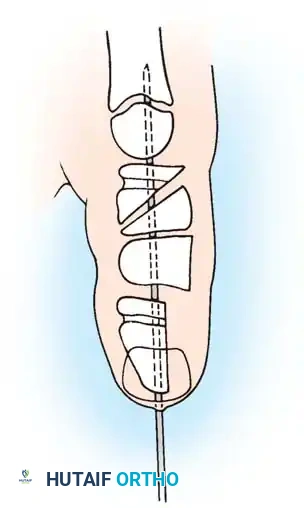

TECHNIQUE 76-52: Release of a Congenital Trigger Finger

Surgical management of a trigger finger requires a more extensile approach due to the high likelihood of complex FDS/FDP interactions.

- Incision: Make a volar zigzag (Bruner) incision centered over the A1 pulley to allow for both proximal and distal exposure of the flexor tendon sheath and its contents.

- Exposure: Elevate the skin flaps, taking care to identify and protect the digital neurovascular bundles bilaterally.

- A1 Pulley Release: Incise the A1 pulley completely from its proximal to distal extent.

- Dynamic Assessment: Passively flex and extend the digit. Inspect the motion of the flexor tendons. If normal gliding of the FDS and FDP is present and triggering has resolved, proceed to closure.

- Extended Exploration (If Triggering Persists):

- Inspect the FDS tendon for a more proximal-than-normal decussation (chiasm of Camper) or an abnormal insertion into the FDP tendon.

- If an abnormal FDS slip is tethering the FDP, excise one or both slips of the FDS tendon to decompress the sheath.

- Inspect the A3 pulley. If triggering occurs at this level, carefully release the A3 pulley, ensuring the A2 and A4 pulleys remain strictly intact.

- Final Verification: Apply proximal traction to both flexor tendons together and individually in the palm, and passively extend the finger to verify complete resolution of triggering.

- Closure: Close the skin with absorbable sutures and apply a soft hand dressing.

Intraoperative view demonstrating the excision of an abnormal FDS slip to relieve persistent triggering after A1 release.

Biomechanical illustration showing the relationship of the FDS and FDP tendons within the digital sheath.